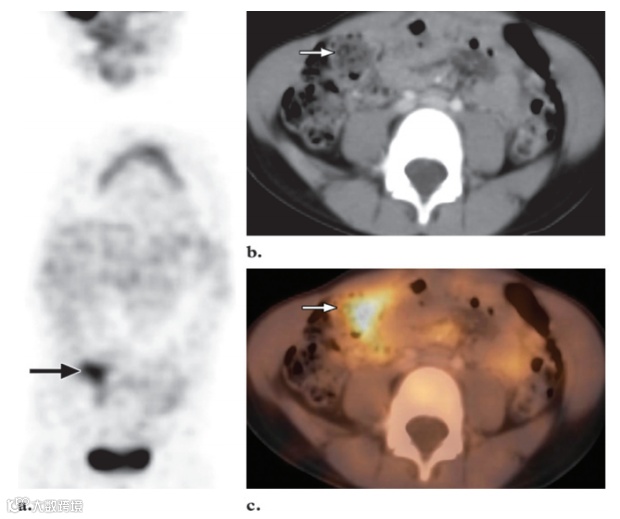

图10. 冠状FDG PET 扫描 (a) 和横向CT (b) 以及融合PET/CT (c) 图像显示正常右结肠中18F FDG 摄取显著增加 (箭头) 。还请注意冠状图像上胸腺中的生理摄取。

小肠的摄取情况多变,可见时通常为低摄取。结肠摄取程度变异极大,可能非常明显,影响整个或部分结肠。盲肠的摄取通常比结肠其他部分更明显,可能是因为回盲部淋巴组织含量更高(图10)。有时,盲肠的强烈摄取可能使恶性肿瘤或炎症与正常病变的鉴别变得相当困难。PET/CT可以与正常肠道直接进行解剖关联,从而减少诊断的不确定性,从而更准确地解释图像。炎症性肠病儿童可见明显的18F FDG 蓄积。肝脏通常显示均匀的中等摄取,脾脏的摄取相对较弱。